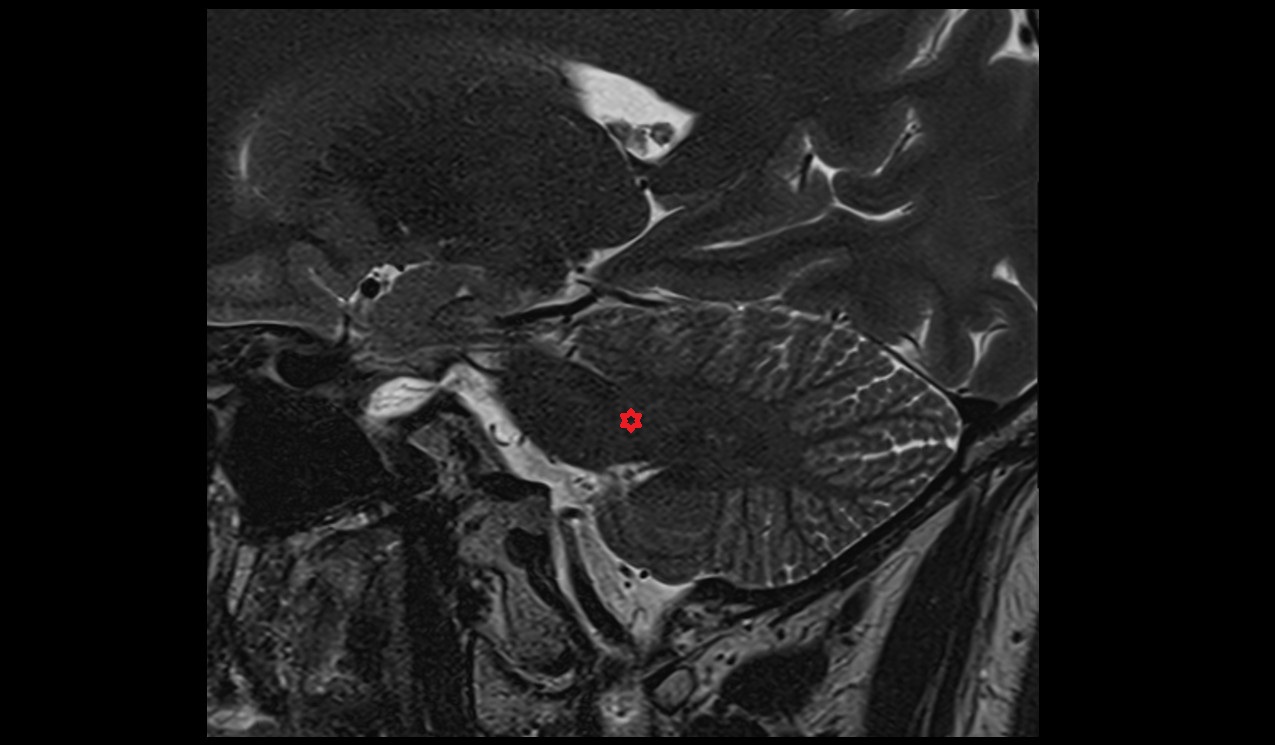

- Uterus

- Body of uterus

- Fundus of uterus

- Cervix of uterus

- Isthmus of uterus

- Endometrium of uterus

- Myometrium of uterus

- Perimetrium of uterus

- Junctional zone of uterus